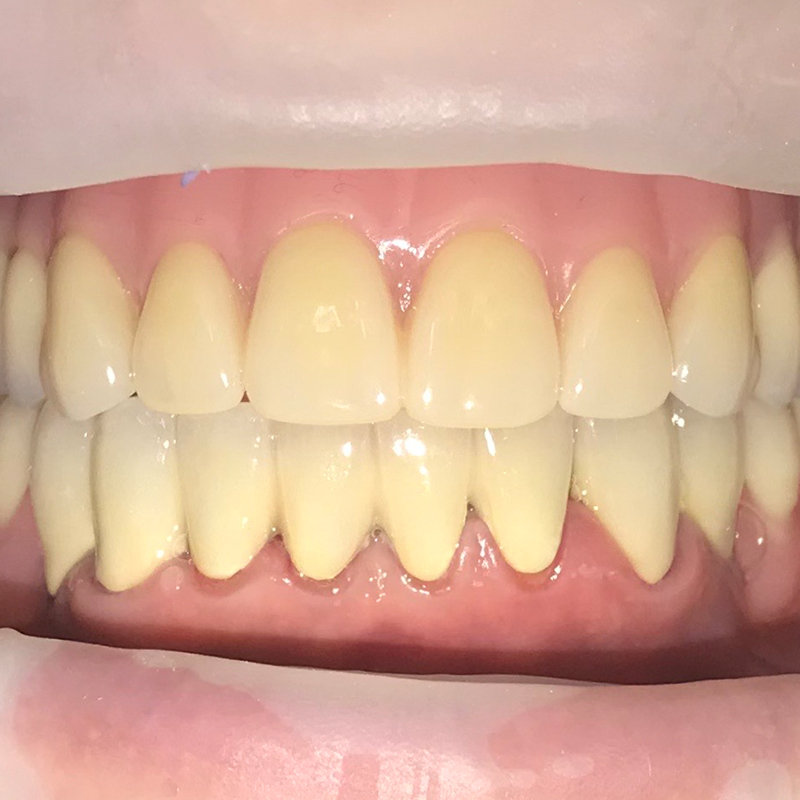

Пациентка обратилась в «Стоматологию Комфорта» с жалобой на отсутствие зубов верхней челюсти. По результатам обследования врач стоматолог-ортопед, хирург-имплантолог Мельников Алексей Владимирович назначил имплантацию по методу «all-on-4». По истечении 6 месяцев после операции проведено обслуживание условно-съёмного протеза. Также врач начал восстановление нижней челюсти коронками в комбинации с бюгельный протезом.

- имплантация по методу «all-on-4» с установкой протеза;

- обслуживание условно-съёмного протеза по истечении 6 месяцев;